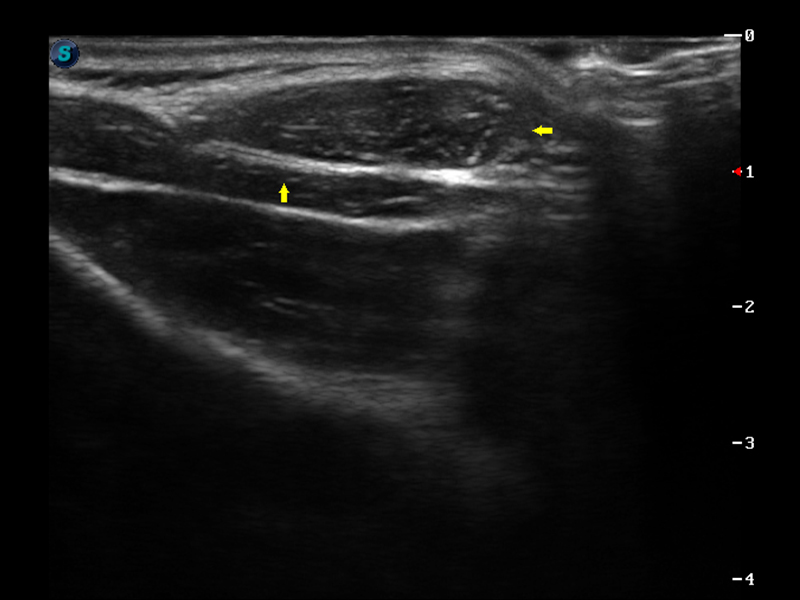

S9便携式彩色多普勒超声诊断仪是竞技宝(JJB)官方网站研发的高端便携彩超设备,外观设计新颖、产品性能卓越。S9在便携超声领域采用了突破传统的触摸屏交互设计,并以先进的软件硬件技术和设计理念,为您带来清晰的图像质量、稳定的工作性能和便捷的操作体验。

μ-Scan微米成像